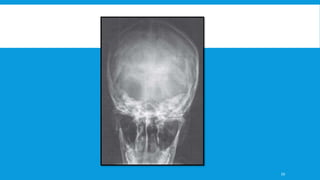

B. Reverse Towne's view and PA mandible –

 The reverse Towne's view gives a good representation of the proximal and distal

fragments in a medio-lateral plane.

 For the measurement of condylar process displacement, coronal displacement is

evaluated with Towne’s radiograph

 It shows the condylar heads much better than the more conventional PA or AP

views of the mandible where these structures tend to be superimposed on the image

of the base of the skull, although the latter views are still useful in the overall

assessment of the injury.